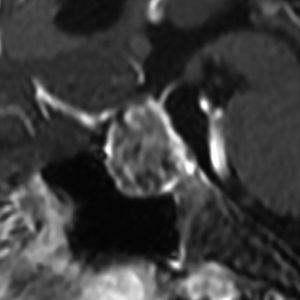

成人の第3脳室内部に局在する頭蓋咽頭腫です。経脳梁法で両側のモンロー孔から全摘出しました。下垂体組織は残っています。これは乳頭状頭蓋咽頭腫と呼ばれるもので,成人にしか発生しません,のう胞がなく石灰化もないのが大きな特徴です。境界が明瞭で柔らかく摘出が簡単なタイプとして知られています。この患者さんも術後に下垂体機能不全も視床下部障害も生じませんでした。